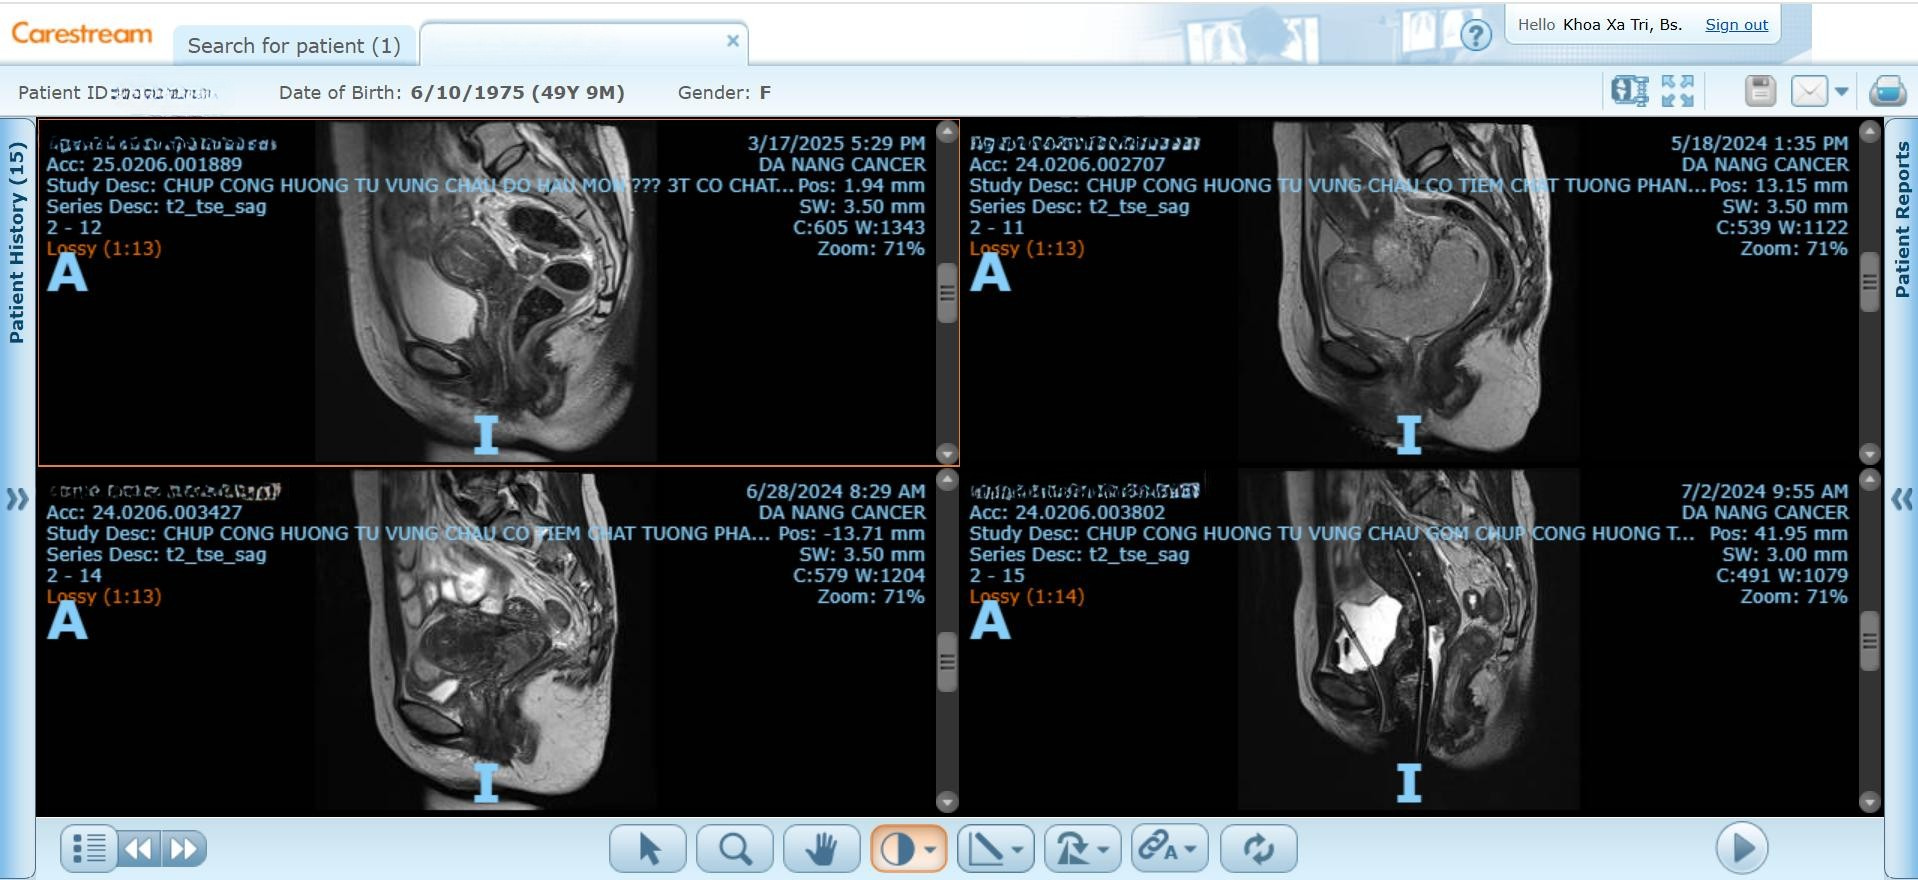

Nhờ ứng dụng kỹ thuật xạ trị áp sát dưới hướng dẫn của CT hoặc MRI, đội ngũ bác sĩ có thể:

- Xác định chính xác kích thước, thể tích và vị trí khối u.

- Cá thể hóa liều xạ cho từng bệnh nhân.

- Đảm bảo tối ưu hóa hiệu quả và giảm biến chứng.